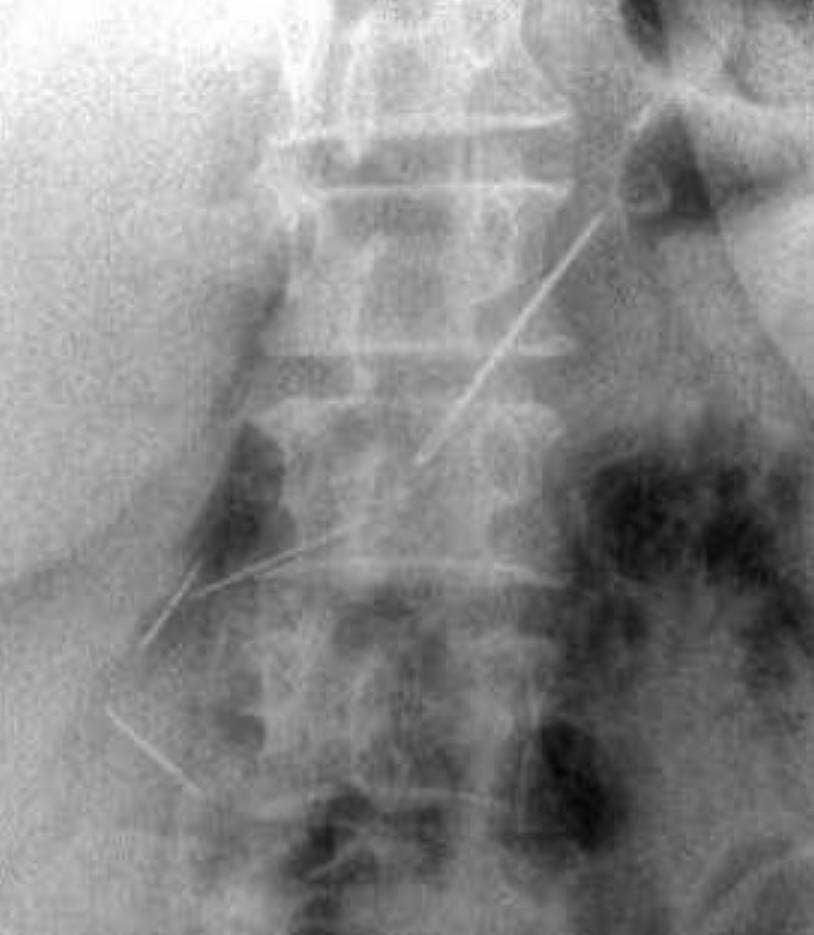

Пожилая женщина обратилась в Красногорскую больницу с жалобами на боли в животе. Пациентку обследовали и выяснили, что у нее в брюшной полости и одной передней брюшной стенке находятся четыре иглы.

Выяснилось, что женщина проглотила их около месяца назад — при каких обстоятельствах это случилось, не уточняется. За время нахождения в организме иглы успели обрасти тканями.

Медики провели пациентке лапаротомию и удалили все инородные предметы. Одна из игл проникла в поджелудочную железу, но орган все же удалось сохранить. Вмешательство прошло успешно.